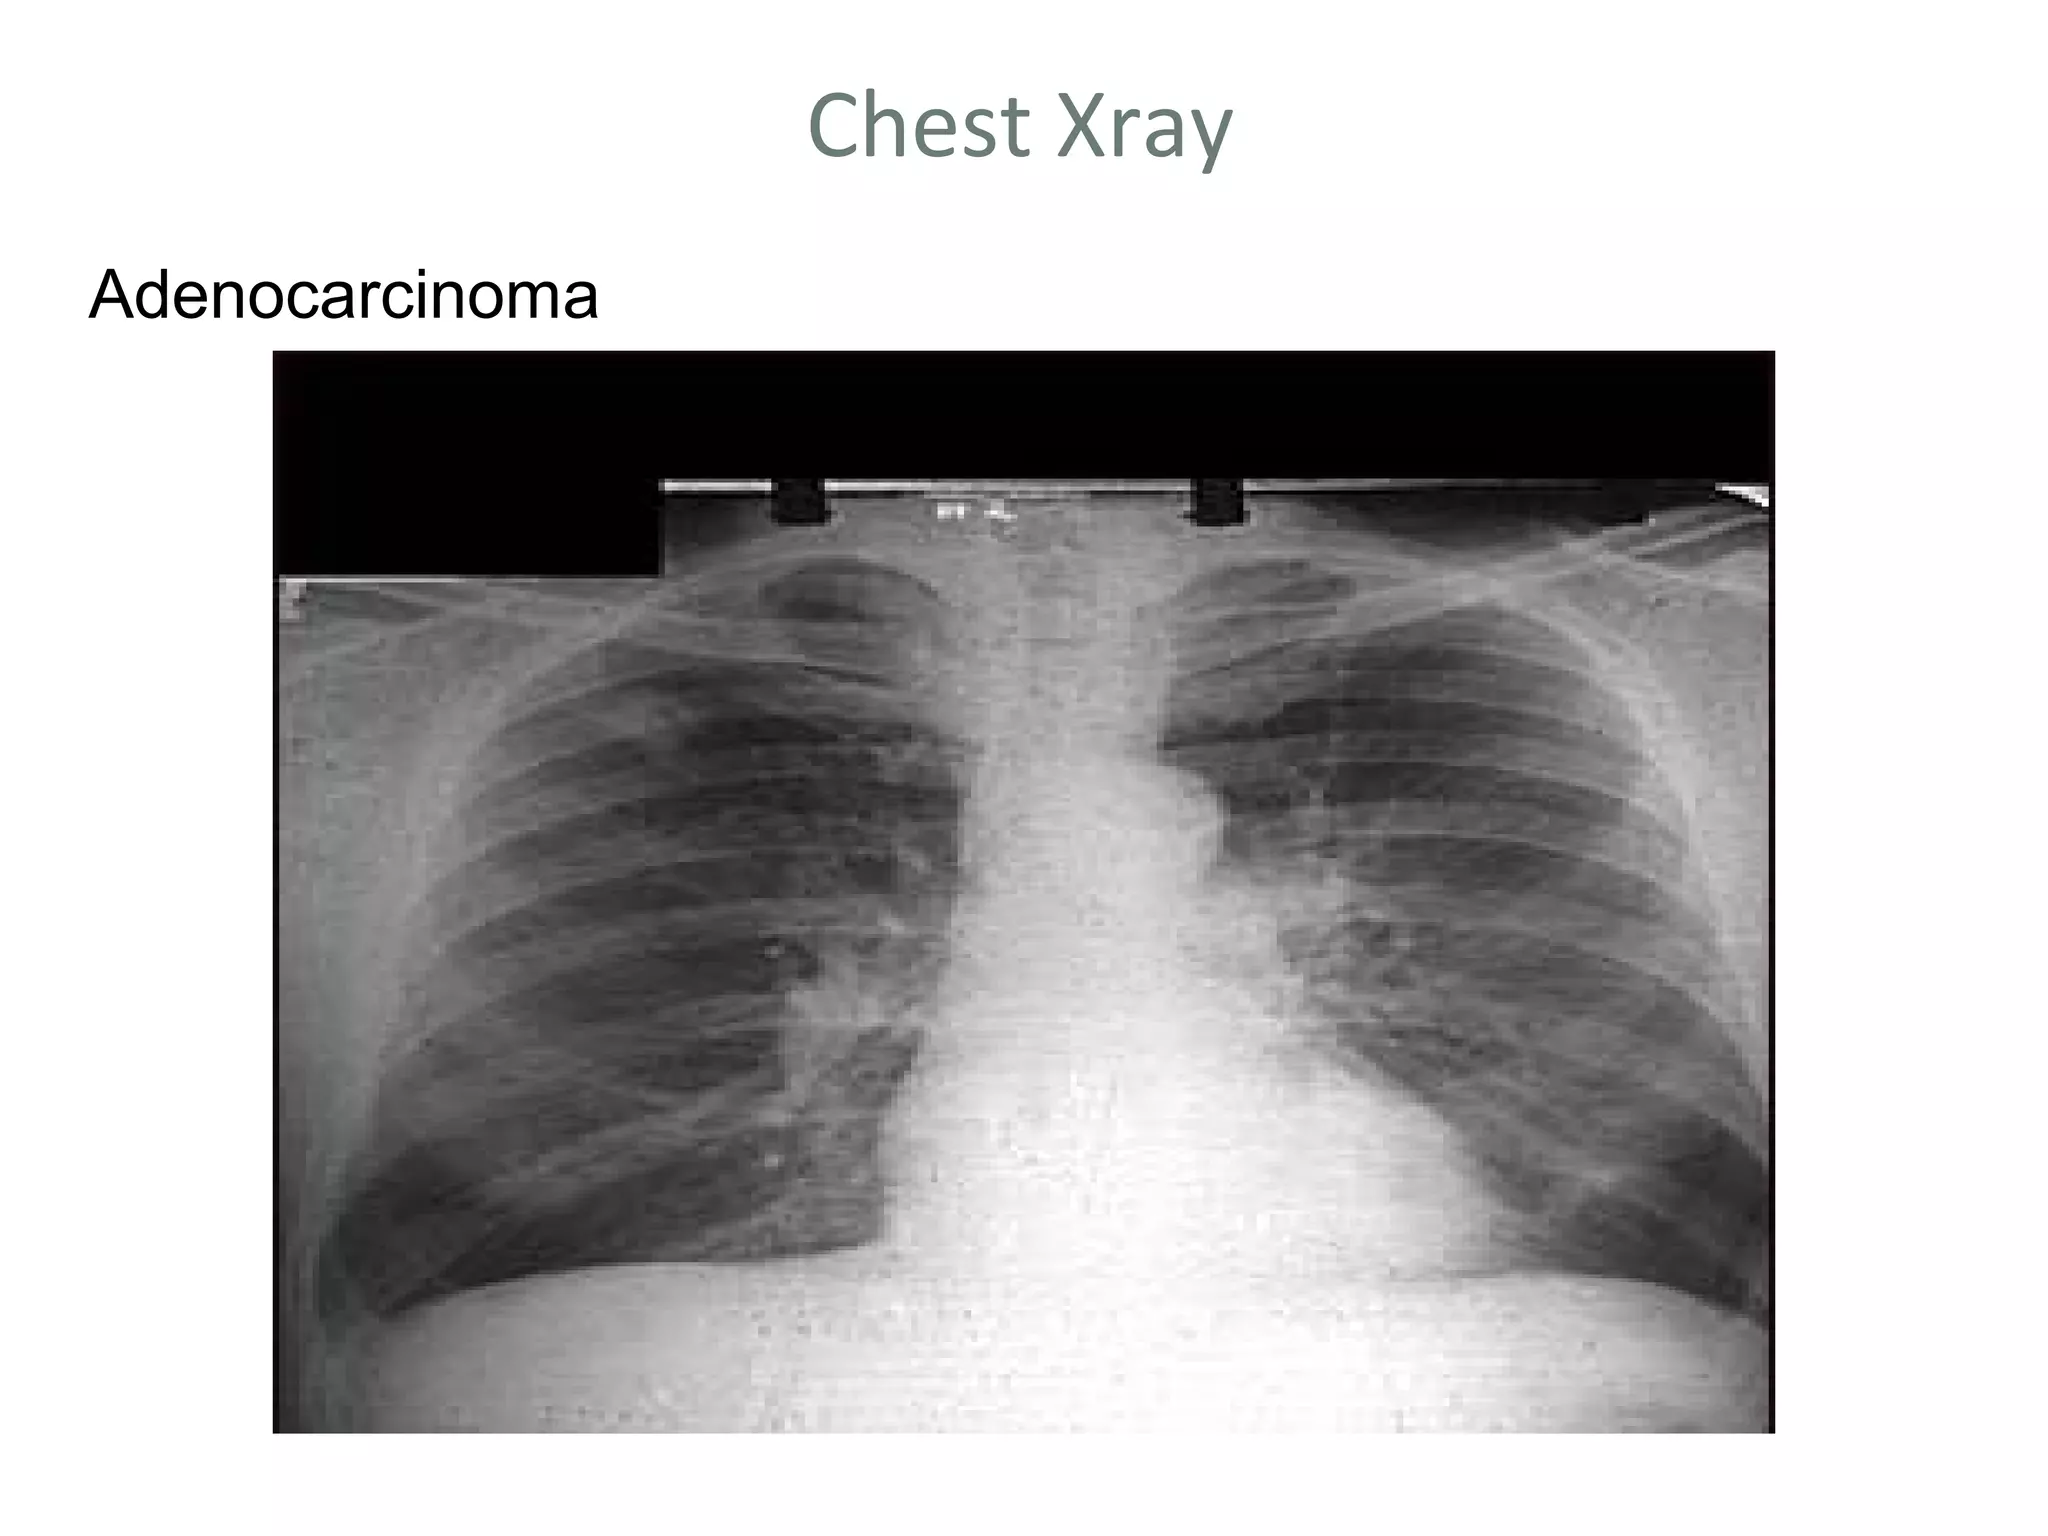

Chest Xray

Adenocarcinoma